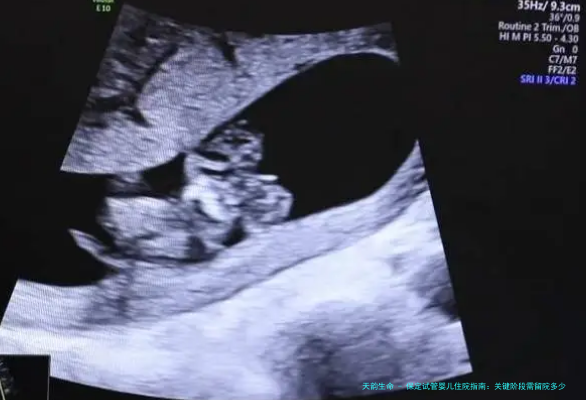

跟着医疗流程的完善,保定区域试管婴儿住院时间逐年减短。本文细致解说各阶段住院时长及注意事项。

胚胎移植阶段

鲜胚移植需住院24小时,冻胚移植建议48小时。生殖医学中心王主任强调子宫内膜厚薄程度达目标重要性。